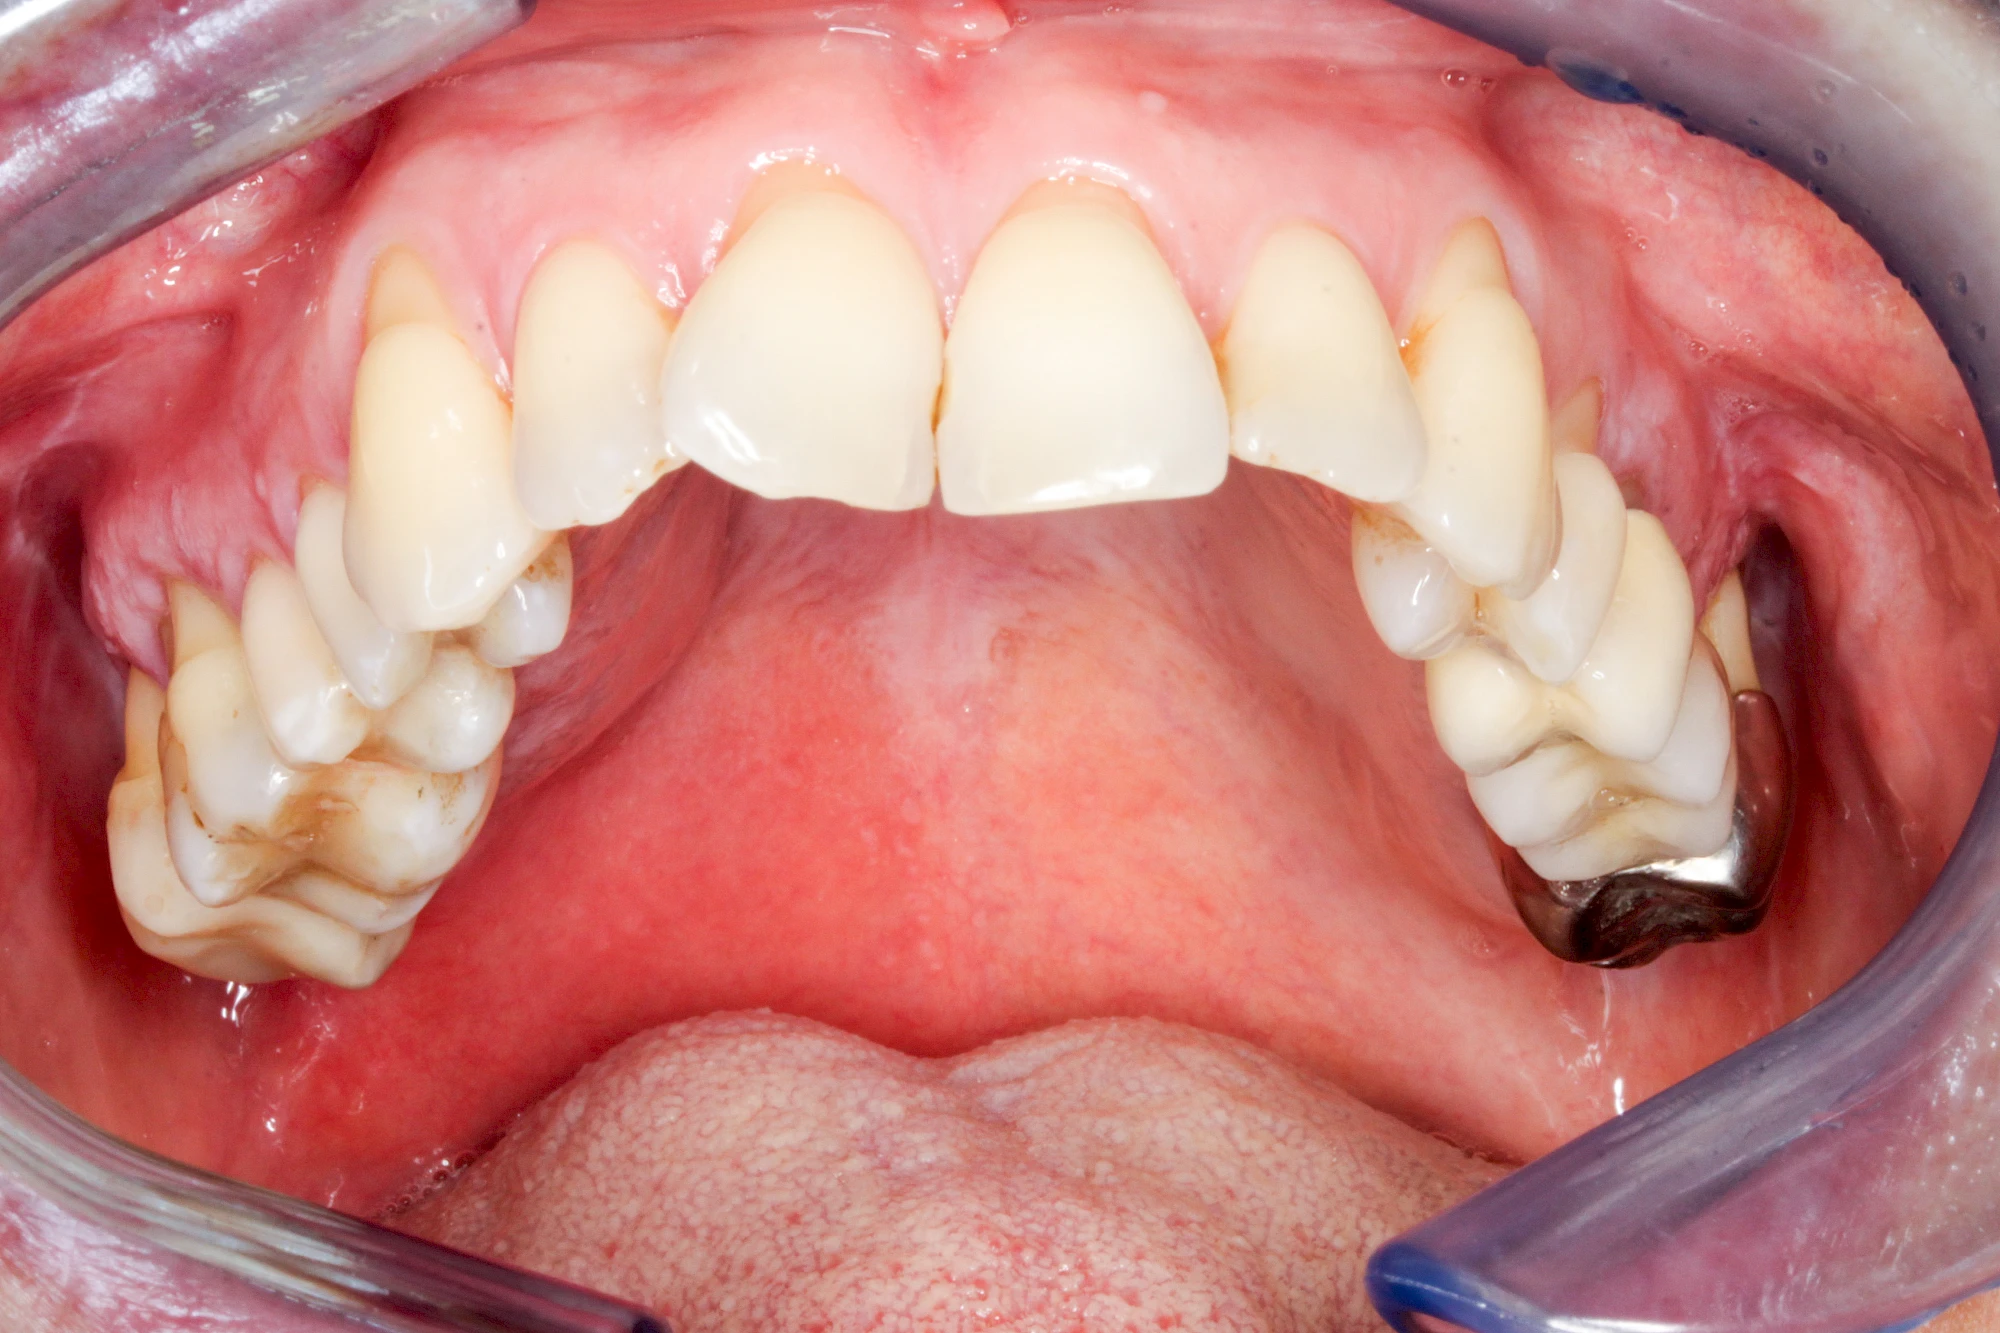

Diese Vermehrung von Bindegewebe in einem frei gewordenen Raum ist eine Sonderform der Anpassungsreaktion menschlicher Zellen und wird als Vakatwucherung bezeichnet.

Früher wurden im Unterkiefer mitunter Brücken zum Ersatz fehlender Zähne als sogenannte "Schwebebrücken" gestaltet. Die Idee dabei war, dass man die Brücke insgesamt besser reinigen kann. Allerdings war das für die Patienten mitunter irritierend für die Zunge und vor allem beim Essen gewöhnungsbedürftig. Teilweise haben sich hier reaktiv Vakatwucherungen der Kieferkammschleimhaut gebildet und den Raum unter der Brücke wieder verschlossen.

Vakatwucherung